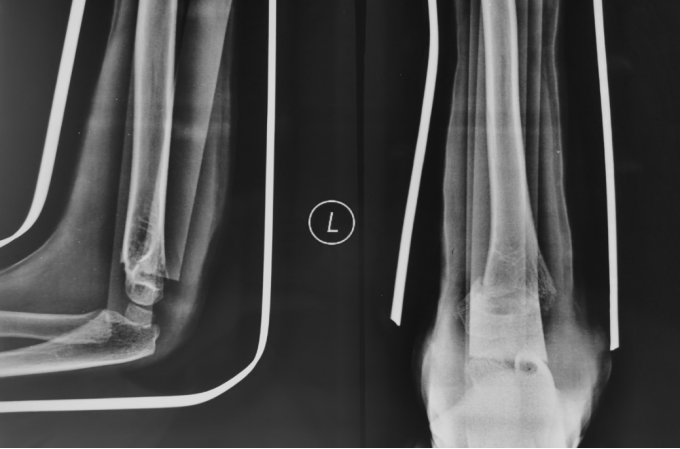

3、小林(化名):男、4岁、在家里从双层床上摔下致左肘部肿痛、畸形、活动受限4小时就诊我院。(下图为患儿术前X线片)